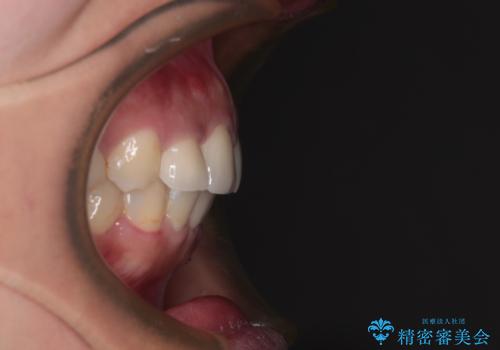

歯列から飛び出た歯 ワイヤー矯正で整った歯列に

- 下顎の歯列から飛び出した小臼歯を気にして来院された患者様です。

歯列以外に、上顎左右側切歯が矮小歯であり、上顎4前歯は失活していたため、矯正治療で歯列を整えるとともに上顎前歯の幅を調整し、矯正治療後にオールセラミッククラウンにて審美歯科治療を行うこととしました。

矯正治療は、小臼歯1本分を歯列に納めないいけない状態であったため、表側のワイヤー装置にて行うこととしました。